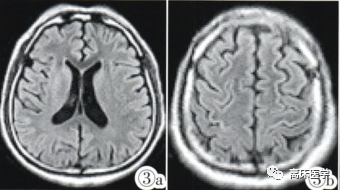

6天后复查MRI:

图:双侧尾状核.壳核及额叶皮层见对称分布T2-flair(3a,3b)及 DWI(3c,3d)呈稍高信号。

最终诊断:渗透性脱髓鞘综合征。